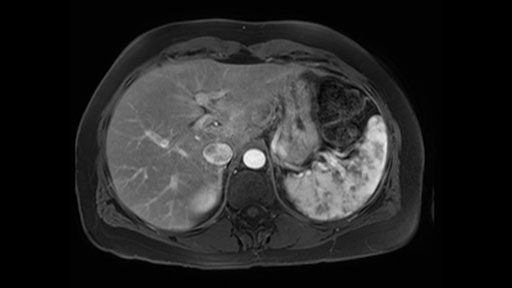

In reviewing this patient’s CT scan, first of all, the lesion is again cystic with a very thin wall. I anticipate that it will be delicate and potentially friable. And therefore the risk of rupture exists and we need to be very careful in how we handle the pancreas and the tumor throughout the procedure.

The lesion itself is quite adjacent to and abuts the splenic vein and therefore we need to anticipate that these two structures will be intimately related and possibly impossible to separate between the two.

The lesion also is quite posterior. While the plane between the cyst and the left adrenal gland is often preserved, we do have to pay attention here so that we remain in the right plane and maintain our margin here. Occasionally in these cases, en bloc adrenalectomy needs to be performed.

The preoperative MR is very very important; any scan for that matter. Whether it is a pancreatic protocol CT scan or the MR as presented, the diagnostic imaging plays a very big role. And with this we see that it’s a very well-defined cystic focus in the body of the pancreas. Although there are septal enhancements, very well demarcated, but there is no vascular involvement. However, the mass appears to be in contact with the splenic vessel, and the mass is also a little bit in touch with the left adrenal and also the loop of bowel. So looking at this, basing on the features, I think it’s probably a mucinous cystic lesion, it could possibly be a pseudocyst. But basing on the history, it appears like there is no history that would point out to a pseudocyst. And not an IPMN as well; I don’t see any side branches from the MRCP and the MR scan and although there is no axial T2 images available, and I truly find it easier to identify the septations on T2, and the hepatic cyst that is visible on this scan makes it hard to differentiate it from a simple or complex cyst which may be considered in a mucinous neoplasm with cystic or mucinous metastasis. Basically the contrast would help us in identifying the enhancing mural nodules or septations in the cysts. The MRCP is definitely helpful to identify if there is any side branch, if we are considering any IPMN.

So first, I'll show you the scan. Here's the traditional view, where you see the cyst, which is in the body of the pancreas. And you see over here, it's got a quite thick wall. And going a little bit back also, here you see a septation which is very important, because I think a septation is what separates this from, for instance, the pseudocyst of the pancreatitis. And also the location of the cyst you see here, abutting the adrenal gland and going down a bit more, it's also quite close to a bowel loop. So when thinking about this cyst: female, the location in the body of the pancreas, thick wall, septation, and as you can read in history, it was basically asymptomatic, so no signs of pancreatitis. So, this probably all points towards a mucinous cystic neoplasm.